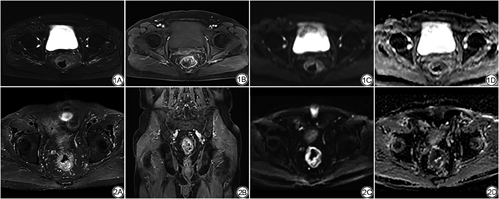

常规MRI+DWI评价T、N分期及CRM整体准确率分别为83.3%、81%、83.3%,与病理结果比较一致性均较好(Kappa值分别为0.745、0.691、0.642,P<0.01) (表2, 3, 4)。常规MRI+DWI对直肠癌T、N各期及CRM的诊断效能(准确率、敏感度、特异度、阳性预测值、阴性预测值)见表5。典型直肠癌影像见图1、2。

由2名经验丰富的副主任医师以上职称的放射科医师分别进行阅片,判断出T、N分期,以及CRM是否受侵,若诊断结果不一致,则经协商讨论取得一致结果作为最终结果。直肠癌分期根据美国癌症联合委员会直肠癌TNM分期标准(第8版)[4]。常规MRI上T1、T2期病变表现为黏膜线中断,肠壁增厚,但未突破肠壁外缘,肠壁外脂肪间隙清晰;T3期表现为肠壁外缘不光整,凹凸不平,可有结节状突出,病变肠壁周围脂肪间隙内有索条状异常信号;T4期肿瘤与周围脏器或结构界限不清或脂肪间隙消失。T1和T2期直肠癌在常规MR图像上分辨较为困难,且临床治疗原则相同,故本研究将两者合并为T1~T2期进行分析[5]。影像学淋巴结转移的形态学标准有:(1)短径≥9 mm伴或不伴有边缘不规则或信号不均匀或呈圆形;(2)短径5~9 mm之间,并伴有边缘不规则、信号不均匀、呈圆形三个征象的其中两个征象;(3)短径≤5 mm,并呈圆形,且边缘不规则、信号不均匀[6]。CRM是指肿瘤到直肠系膜筋膜的距离,直肠系膜筋膜在常规MRI上表现为包绕直肠系膜脂肪的线状低信号,当肿瘤的最外缘、直肠系膜内转移淋巴结、癌结节或受侵的血管与筋膜的最短距离<1 mm时,则视为CRM受侵(CRM阳性)[7]。